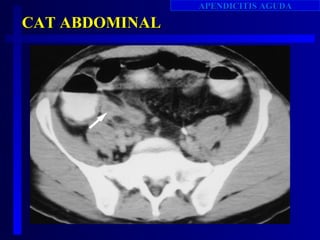

CAT ABDOMINAL

Sens. 87% - 100% -     Espc. 84% - 97%

Mayor costo

Exposición a radiaciones

Exposición a medios de constraste

Disponibilidad

Operador dependiente

No ha mejorado el pronóstico

Surg Clinics Nort Ame Vol. 77: 6; 1997

•Indicación:

•Ecografia no concluyente.

•Ecografia normal pero persiste duda.

•Pacientes cuadro atípico.

•Edad avanzada

•Inmunosupresion.

Patrick M.Rad Clinics N A, Volume 37. Number 5 . September 1999

Patrick Rao . N.E.J.M, january 15, 1998, vol 338, Number 3.

•Apéndice anormal mide mas de 6 mm diámetro y es el

mas fuerte predictor.

•Falla para llenar con el contraste

•Apendicolitos intraluminales.

•Grasa anormal, líquido , burbujas de aire extraluminal,

•Engrosamiento cecal apical.

• Signo de punta de flecha

• Barro cecal.